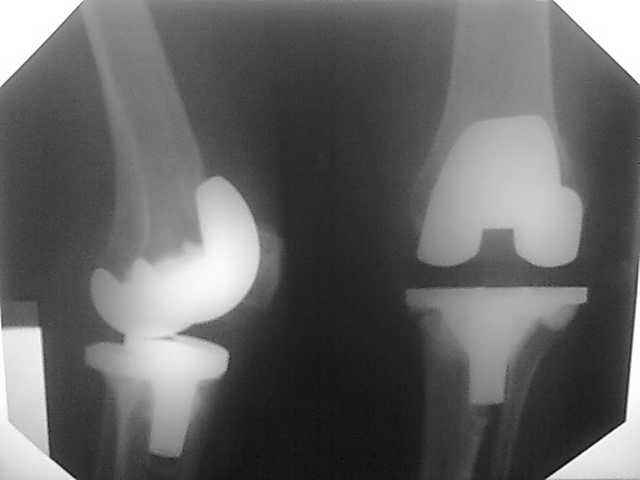

Уважаемые коллеги, прошу Вашего совета по тактике лечения. Женщина 1952 г.р., оперирована в 2006, в одной клинике установлен эндопротез правого коленного сустава, через год нестабильность обоих компонентов, доктор выполняет ревизию обычным протезом с задним стабилизатором. В октябре 2008 - нестабильность, свищ. В другом стационаре все удалено, спейсер с гентамицином, длинный курс антибиотиков. Коллатеральных связок нет. Собственная связка надколенника цела. До удаления протеза - выраженная смешанная контрактура. Сейчас свищей нет, анализы в порядке.

Планы: Стоит выбор 1) Обычный hinge с цементными ножками, вставками под тибиальным и бедренным компонентами с импакционной костной пластикой аллокостью с применением сеток для удержания трансплантата на tibia; 2) Онкологический hinge - с замещением проксимальной голени и сохранением бедра; 3 - артродез.

Александр Николаевич - это просто то, что мы можем сделать исхоя из наличия бесплатных (условно) имплантов и наших навыков работы с ними. Простой hinge - Страйкеровский MRH или онкологический - GMRS, сетки Exchange, артодез - думали над ИМ артродезным гвоздем с аллотрансплантатом. Больная совсем молодая женщина...

Мне очень хотелось узнать мнение коллег на предмет - если ставить простой hinge с костной пластикой - стоит ли использовать только костную крошку или необходим структурный костный аллотрансплантат? Есть ли у кого-то положительный опыт таких операций? Душа у меня не лежит использовать онкологическим протез для голени, т.к. пациентка слишком молода и сохранена собственная связка надколенника.